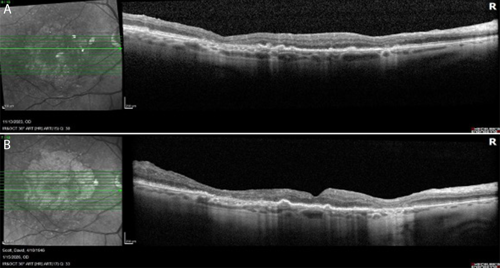

Throughout more than 2 years of treatment OD and 9 months OS, VA has remained stable at 20/40 bilaterally. FAF imaging at approximately 2 years demonstrates continued GA enlargement OD, though with preservation of a central foveal island (Figure 2b). OCT confirms stable foveal architecture despite peripheral atrophic progression (Figure 3). No adverse events have been observed, and the patient continues his active lifestyle.